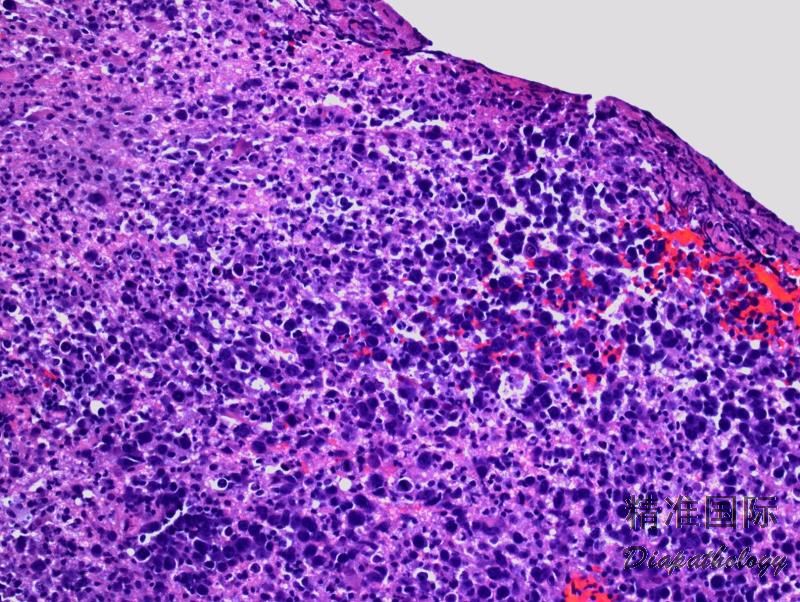

肿瘤细胞呈现弥漫浸润性生长,边界模糊;也可呈现斑片状或血管中心性浸润 (特征性浸润血管周围间隙)。可见单个细胞或地图样坏死。

肿瘤细胞中到大,核圆、椭圆、不规则或多形,可与中心母细胞或免疫母细胞较相似,常混有反应性小淋巴细胞、巨噬细胞和胶质细胞。